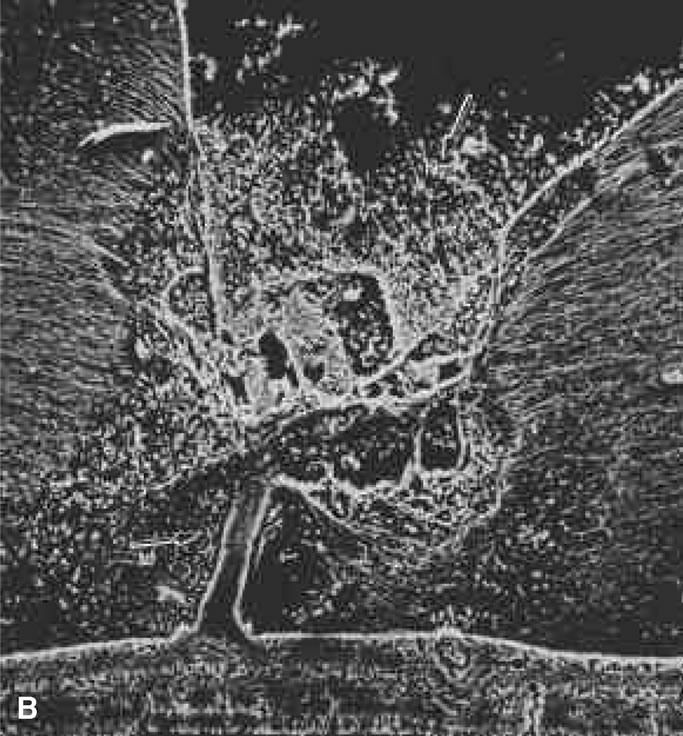

Lindner111 and Jaffe112 described that in some cases of PVD, there is herniation of vitreous through the vitreous cortex of the posterior pole. As previously mentioned, Gartner67 drew an analogy between this phenomenon and the herniation of the nucleus pulposus in the intervertebral disks of the spine. When a PVD involves herniation of the vitreous into the retrovitreal space by way of the premacular vitreous cortex, there can be persistent attachment to the macula and traction (Fig. 9).113

Fig. 9. Vitreomacular traction. Vitreous can remain attached to the macula even in the presence of posterior vitreous detachment. In such cases, vitreous can extrude through the premacular vitreous cortex and fibers can insert into the macula. B, C, and D are an artist's rendition of this phenomenon. A demonstrates vitreous extrusion into the retrohyaloid space in a specimen from a middle-aged human. (Adapted from Jaffe NS: The Vitreous in Clinical Ophthalmology. St. Louis, CV Mosby, 1969; and Jaffe NS: Vitreous traction at the posterior pole of the fundus due to alterations in the posterior vitreous. Trans Am Acad Ophthalmol Otolarynogol 71:642, 1967.)